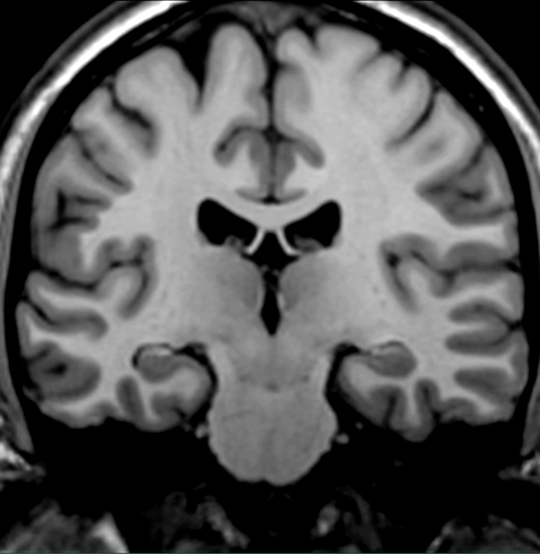

Identify the structure which shows a depletion of neurons and shrinkage of tissue (sclerosis) in patients with complex partial seizures.